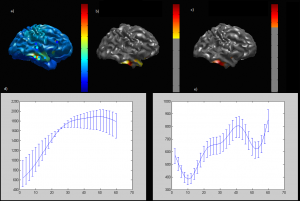

- Computational Imaging Laboratory

https://bme.bogazici.edu.tr/en/computational-imaging-laboratory

Field of Study: Magnetic resonance imaging techniques (MR spectroscopic imaging (MRSI), arterial spindle labelling (ASL), diffusion tensor imaging (DTI), etc.) are used to identify anatomical, physiological and biochemical changes due to brain diseases, classification of medical image data for disease diagnosis using machine learning and deep learning methods, and image enhancement (super enhancement).To identify anatomical, physiological and biochemical changes due to brain diseases using magnetic resonance imaging techniques (MRI), classification of medical image data for disease diagnosis using machine learning and deep learning methods and image enhancement (super resolution), to accelerate routine MRSG techniques used in the clinic, To develop quantitative molecular MR imaging techniques for more sensitive and accurate data acquisition and processing, to develop modelling and analysis methods to create MR parametric maps, to develop user-friendly data analysis interfaces, and to produce phantoms that mimic brain chemistry and anomalies.